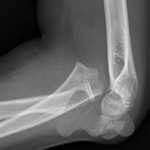

Dislocations are commonly a result of trauma causing the joint to move out of its normal position and relationship with other bones. Dislocations can be accompanied by fractures. Sometimes the dislocation causes an obvious deformity and can be pulled or pops back into position on it’s own. In some situations, the joint cannot be pulled back into position or keeps falling out of position due to tissues such as bone fragments blocking the reduction or due to torn ligaments or fracture through supporting bones. In this situation, you may need to have some form of anaesthetic to realign the bones in the Emergency department or operating theatre or in some cases, the joint being opened and surgically stabilised.